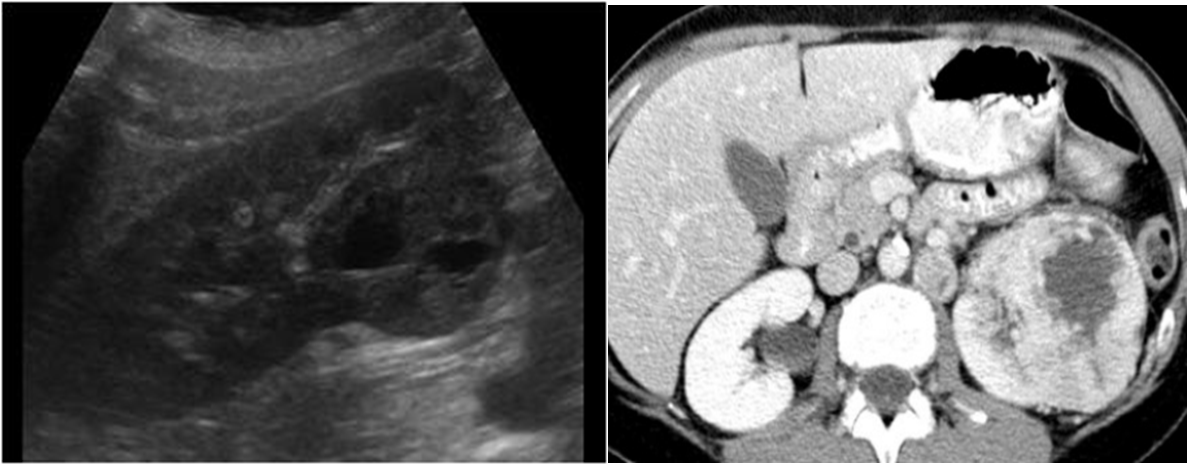

Middle age male patient presents with painless hematuria and weight loss.

- CT and ultrasound show mass lesion in left kidney

- Diagnosis: renal cell carcinoma